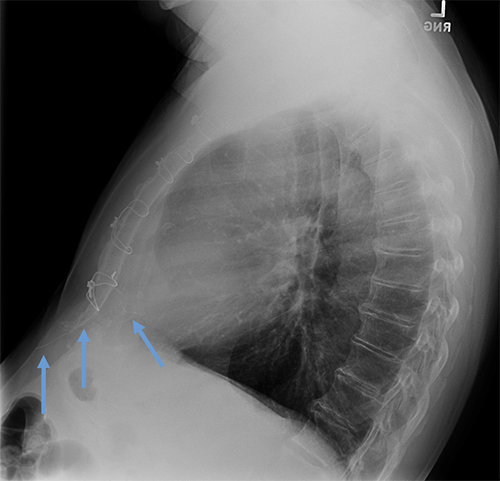

- CEID images with lead types:

Pacemaker with transvenous leads

Pacemaker with epicardial leads

Defibrillator lead

Subcutaneous defibrillator

Cut epicardial wires (often hard to see)

Abandoned leads

Abanded leads plus generator

Temporary transvenous lead

Leadless pacemaker